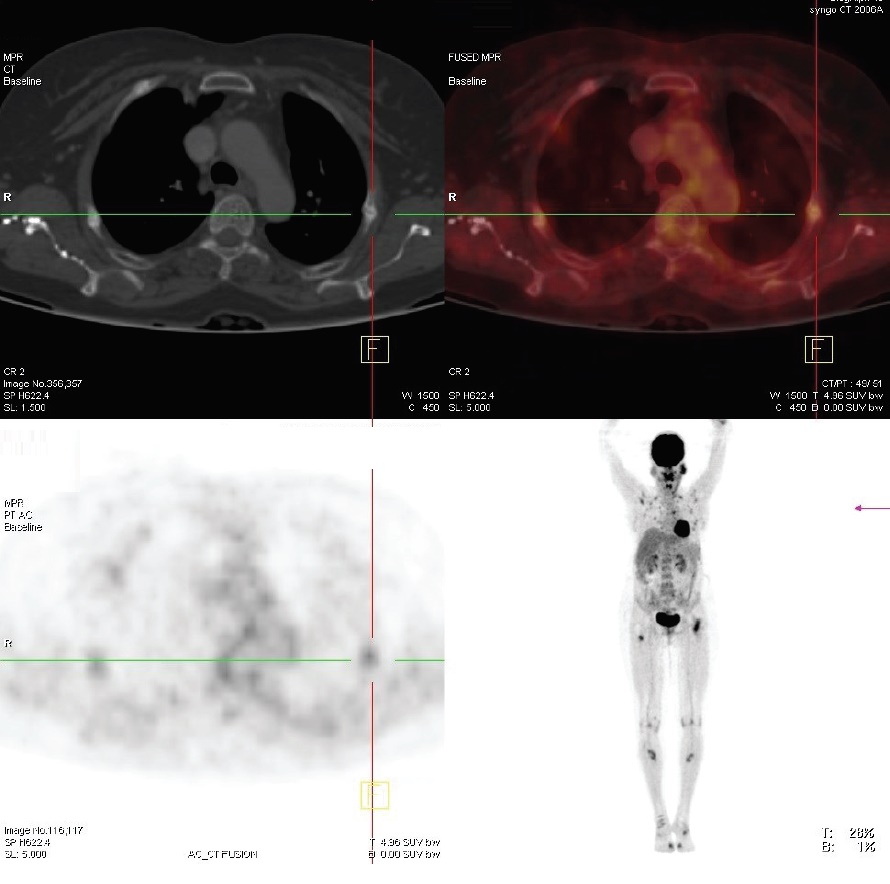

Radiological studies showed bilateral tibial shaft fractures, multiple fractures in bilateral tarsals (Figures 1 to 3). A PET Scan showed multiple insufficiency fractures of bilateral tibia, neck of right femur, metacarpal bones and scapula (Figures 4 to 7).

Figure 4.PET scan showing uptake over fracture part.

Figure 5.PET scan showing fracture of ribs.

Figure 6.PET scan showing fracture of tibial shaft.

Figure 7.PET scan showing multiple fractures.

Since the parotid tumour also has a mesenchymal component, it was thought to be a source producing FGF23. (68)Ga-DOTATE scan was done which showed increased uptake over left parotid, SUV (Standard uptake values) max – 97.5, other areas, had normal physiological uptake (Figure 8).

For tumour localisation, imaging modalities such as X-ray, CT and MRI can be used. Some tumours express surface somatostatin receptors. Somatostatin receptor PET scan is used as a diagnostic tool in refractory cases. In our patient Somatostatin receptor PET scan was used as nuclear imaging method. Radiolabelled octreotide was injected in a patient and whole body follow images were taken. Tumours that have surface somatostatin receptors bind to the octreotide and light up images.

TIO is an acquired disorder of renal phosphate wasting that is associated with tumour. Patients with TIO present with hypophosphataemia with inappropriately suppressed 1,25 (OH)2 D concentration. Clinical symptoms include gradual onset of muscle weakness, fatigue and bone pain, especially for ankles, legs, hips and back. Insufficiency fractures are common and proximal muscles weakness can become severe enough for patients to require wheel chair or they become bedbound. This case highlights the importance of measuring serum phosphorus and phosphate clearance in patients with unusual musculo-skeletal pain and myopathic weakness. (68)Ga-DOTATE scan helps in localization of such a tumour and surgical resection can lead to total cure.